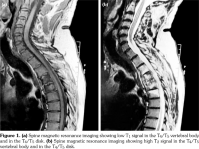

Laboratory examination revealed a slightly elevated C-reactive protein level (16 mg/L) and erythrocyte sedimentation rate (40 mm). Serum levels of calcium, albumin and phosphorus were within the normal range. Blood cell counts, liver tests, and renal function were unremarkable. Blood cultures, urinanalysis, tumor markers, and serodiagnosis for brucella were negative. Tuberculosis skin test was negative. Spine magnetic resonance imaging showed low T1, high T2 signal and contrast enhancement in the T4/T5 and L3 vertebral body and in the T4/T5 disk (Figure 1). Sacroiliac joints were normal. Computed tomography-guided biopsy of the T4/T5 disc demonstrated nonspecific inflammation and culture of this specimen was negative. Computed tomography scan of the sternoclavicular joints revealed hyperostosis and erosions involving the sternum as well as medial end of clavicle (Figure 2). Clavicular biopsy showed irregular sclerotic trabeculae. Human leukocyte antigen B27 typing was positive.

Radiological signs of SAPHO may sometimes be difficult to differentiate from infectious spondylodiscitis and even tumors, leading to a diagnostic delay. Indeed, the intervertebral disc may be narrowed, and, in 10% of cases, magnetic resonance imaging shows high signal intensity on T2-weighted images and gadolinium enhancement, simulating infectious spondylodiscitis.(3-7)